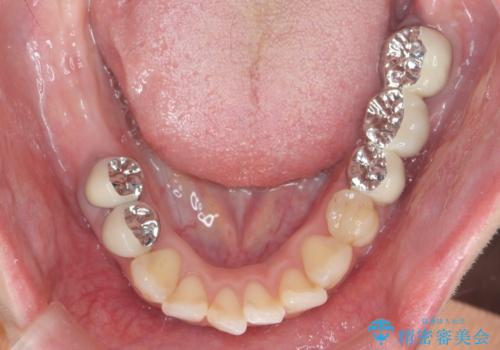

インプラント・セラミック・矯正治療を含む包括歯科診療

- 20代女性

- 「地元の歯医者にずっと通っているが、どんどん歯が悪くなる。時間とお金がかかってもいいので徹底的に歯を治したい。」

、と総合的な歯科治療を希望されて来院されました。

虫歯や咬合関係・歯槽骨の吸収・根尖病変・歯の欠損・複合的な問題を一つずつ解決し、

安定した噛み合わせの構築・歯ブラシのしやすい環境の整備・歯内歯周の感染除去・造骨を伴うインプラント治療

を行い、長期的な予後を見込める口腔内環境を確立、整備して行きます。